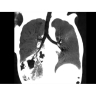

Позволяет проводить комплексные исследования всех анатомических зон, включая нейровизуализацию, ангиографию, исследования органов грудной и брюшной полости. Особенно эффективен для раннего выявления онкологических заболеваний.

КТ-аппараты, Ветеринарные аппараты КТ, Аппараты КТ для легких